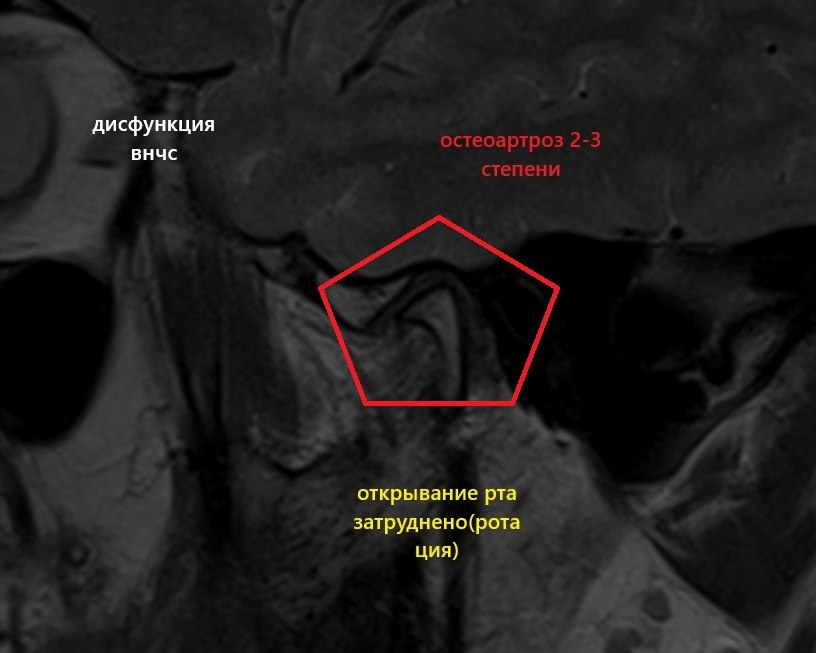

Дисфункция височно-нижнечелюстного сустава (ВНЧС) — это частичная или полная потеря функций сустава: жевания, образования речи. Сопровождается появлением болей различного генеза, щёлканьем в суставе, потерей некоторого объёма движений нижней челюсти, заложенностью в ухе, головными болями, болями в ушах и прочих смежных областях (глазах, шее, спине).

Пациент до ортеза, и после по истечении нескольких дней.